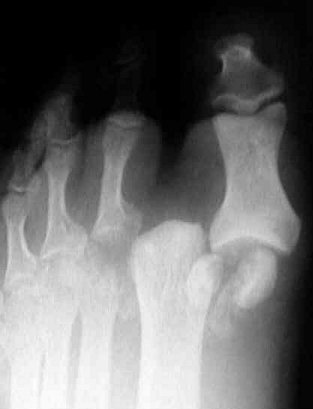

Return to Turf Toe Injury